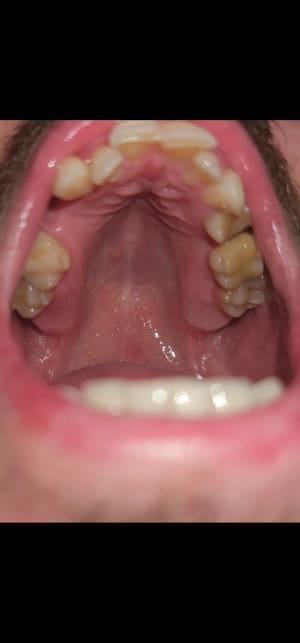

Screenshot_20240126_152859_Gallery.jpg